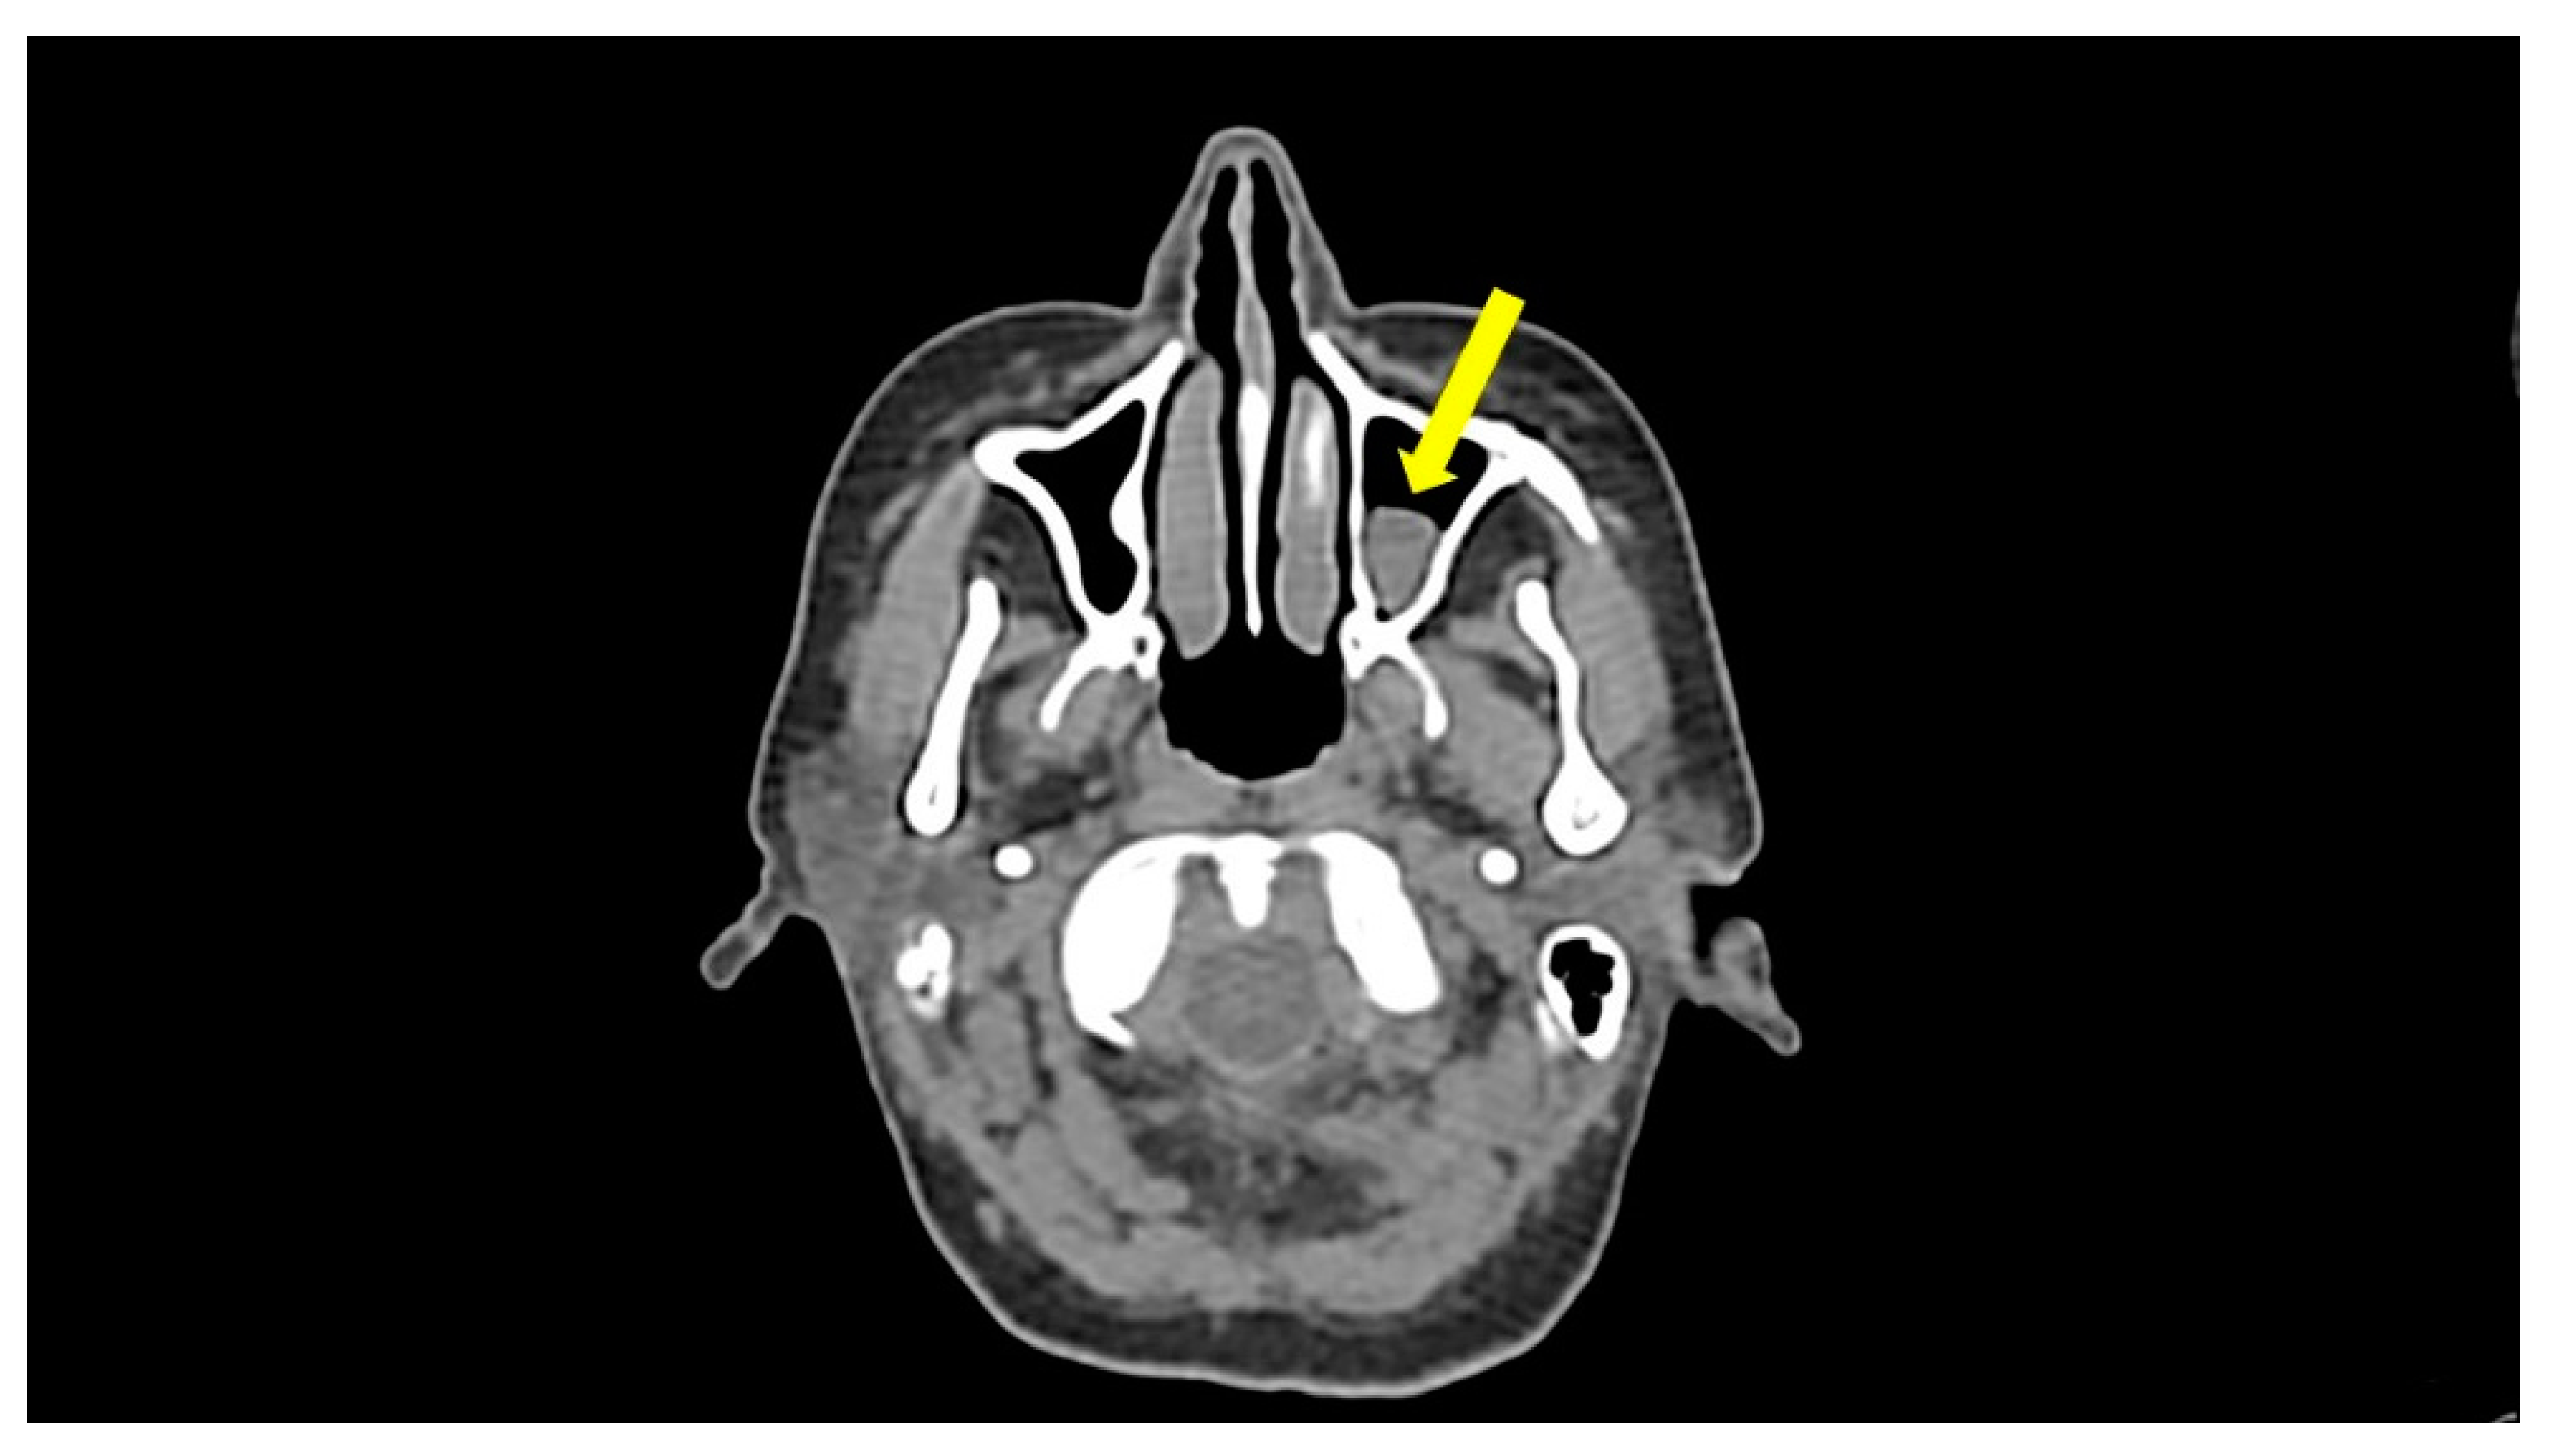

| Maxillofacial CT | Unilateral maxillary sinusitis | - |